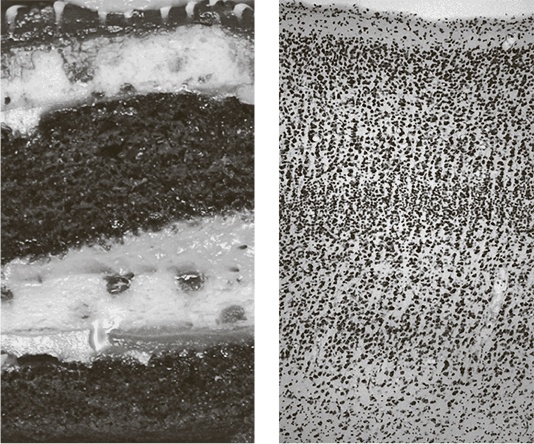

Мы уже выяснили, почему так важно уметь правильно разрезать мозг на отдельные участки. Используя бродмановскую карту, нейробиологи и нейрофизиологи интерпретируют симптомы повреждений мозга. Каждое кортикальное поле связано с одной из умственно-психических способностей (например, со способностью понимать слова или произносить их), и повреждение этой области негативно влияет на эту способность. Но почему важно уметь мысленно делить мозг еще более подробно – по типам нейронов? Достаточно сказать, что такая информация может пригодиться неврологам. Она не так нужна для диагностики и лечения инсульта или других подобных заболеваний, которые обычно затрагивают все нейроны на определенном участке мозга. Но есть мозговые недуги, которые поражают определенные типы нейронов, а другие типы нейронов не трогают. Болезнь Паркинсона (БП) начинается с расстройства контроля движений. Самые заметные симптомы – непрекращающаяся дрожь или непроизвольные подергивания конечностей, когда пациент вовсе не пытается ими шевелить. По мере своего развития недуг может вызывать проблемы в интеллектуальной и эмоциональной сферах и даже приводить к слабоумию. Печальные истории Майкла Фокса и Мохаммеда Али привлекли всеобщее внимание к этому заболеванию [18]. Как и болезнь Альцгеймера, БП приводит к дегенерации и гибели нейронов. На ранних стадиях эти повреждения происходят лишь в базальных ганглиях. Эта замысловатая конструкция укрыта в глубине конечного мозга, она также играет роль в развитии болезни Хантингтона, синдрома Туретта и маниакально-депрессивного психоза. Поскольку эта область причастна к такому большому количеству недугов, можно предположить, что она имеет очень важное значение для функционирования мозга, хотя сама она куда меньше по размерам, чем окружающая ее кора. Рядом с базальными ядрами находится так называемая черная субстанция (substantia nigra pars compacta), на которую и приходится основной удар при нейронной дегенерации в ходе БП. Можно даже выделить конкретный тип поражаемых нейронов. Эти нейроны, выделяющие нейротрансмиттер допамин, в ходе развития БП постепенно гибнут. Пока лекарства от этой болезни не существует, но проявление ее симптомов удается подавить с помощью медикаментов, компенсирующих снижение выработки допамина. Знать о типах нейронов важно не только для лечения болезней, но и для понимания нормальной работы нервной системы. К примеру, пять обширных классов нейронов сетчатки: фоторецепторы, горизонтальные клетки, биполярные клетки, амакриновые клетки и ганглиозные клетки – специализируются на выполнении различных функций. Фоторецепторы воспринимают свет, попадающий на сетчатку, и превращают его в нервные импульсы, покидающие сетчатку по аксонам ганглиозных клеток и затем по зрительному нерву идущие в мозг. Эти пять широких классов затем разделили дальше – на более чем пятьдесят типов. На рис. 38 каждая полоска представляет один класс и содержит изображения типов нейронов, к этому классу принадлежащих. Функции у нейронов сетчатки значительно проще, чем у достопамятного «нейрона Дженнифер Энистон». К примеру, некоторые из них дают пик в ответ на обнаружение светлого пятна на темном фоне, а другие – наоборот, в ответ на обнаружение темного пятна на светлом фоне. Каждый из исследованных на данный момент типов нейронов обладает своей функцией. Ученые стремятся выявить конкретные функции всех нейронных типов. ![]() Рис. 38. Типы нейронов сетчатки В этой главе я постараюсь объяснить, почему разделить мозг по участкам и по типам нейронов не так просто, как кажется. Сейчас мы пользуемся для этого методами, которые изобрели еще Бродман и Кахаль больше века назад, и методы эти представляются всё более старомодными. Коннектомика способна внести еще один важный вклад в науку как таковую – дать ей новые, более совершенные методы виртуального разрезания мозга на отдельные участки. А это, в свою очередь, поможет нам лучше понять те патологические изменения, которые в нем так часто происходят, и лучше разобраться в функционировании нормального мозга. * * * Современная карта обезьяньего мозга (см. рис. 39) навевает мне воспоминания об отцовском атласе. На ее цветных областях значатся таинственные сокращения, а плавные изгибы прерываются острыми углами. Но карты не всегда столь прелестны и невинны. Давайте не забывать, что из-за линий, проведенных на них, не раз сталкивались друг с другом целые армии. Нейроанатомы тоже вели жаркие интеллектуальные битвы за границы между областями мозга. ![]() Рис. 39. Карта коры головного мозга макаки-резус (плоская проекция) Мы уже знакомы с картой коры головного мозга, составленной Корбинианом Бродманом. Каким же образом он ее создал? Окрашивание по методу Гольджи позволило нейроанатомам ясно увидеть отростки нейронов. Бродман применял другой полезный метод окрашивания, изобретенный немецким нейроанатомом Францем Нисслем, который не обращал внимания на отростки, зато сделал видимыми под микроскопом все тела исследуемых нервных клеток. На рис. 40 такое окрашивание показывает кору головного мозга (справа), напоминающую слоеный торт (слева). Тела клеток расположены параллельными слоями, идущими через всю центральную кортикальную плоскость. (Белое пространство между телами клеток заполнено спутанными и переплетающимися нейритами, их окрашивание по методу Ниссля не выделяет.) Границы в коре не так заметны, как в торте, но опытные нейроанатомы могут различить в ней шесть слоев. Этот кусок кортикального торта, шириной меньше миллиметра, вырезан из определенного места кортикального слоя. Вообще-то расположение и количество слоев во фрагментах, взятых из разных мест мозга, различно. Бродман пытался увидеть эти различия под микроскопом и, основываясь на них, мысленно разделил кору головного мозга на сорок три поля (области). Он утверждал, что в каждом участке мозга в пределах одного поля расположение и количество слоев одинаковы и меняются лишь на границах между полями. ![]() Рис. 40. Слои: у торта (слева) и в бродмановском поле 17 (справа), называемом также первичной зрительной корой или зрительной зоной V1 Бродмановская карта коры стала по-своему знаменитой, но ее тоже не следует принимать как незыблемую догму. Существует множество других претендентов на истину. Так, берлинские коллеги Бродмана, супруги Оскар и Сесиль Фогт, применили иной метод окрашивания, разделив кору на целых двести областей. Другие карты предлагали Альфред Кэмпбелл, работавший в Ливерпуле, сэр Грэфтон Смит, трудившийся в Каире, а также венцы Константин фон Экономо и Георг Коскинас. Некоторые границы вскоре оказались признаны всеми исследователями, другие же долгое время вызывали ожесточенные споры. В своей книге 1951 года Персиваль Бейли и Герхардт фон Бонин стерли большинство границ, проведенных предшественниками, оставив на карте лишь несколько крупных областей. |